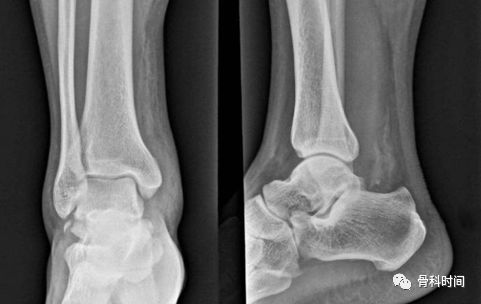

距骨体前宽后窄,外侧前后径比内侧长,以及胫骨远端关节面的外侧宽内侧窄等特殊解剖结构造成了崴脚的高发生率,大约 85% 的踝关节损伤发生在外侧。

踝关节外侧韧带主要是跟腓韧带、距腓前韧带和距腓后韧带。发生崴脚后,外侧各韧带以及起止点均有机会发生损伤及撕脱骨折。

其中距腓前韧带是防止距骨向前移位的主要结构,该韧带最薄弱,踝关节内翻损伤中最容易伤及,可造成距骨止点处撕脱骨折。

踝内翻损伤造成距腓前韧带距骨止点处撕脱骨折

各类型撕脱骨折由于撕脱骨块较小或被重叠往往出现 X 表现的假阴性,另外由于患者不重视,未摄片检查以及采取不正当的处理措施,均容易遗漏撕脱骨折及韧带损伤的诊断。